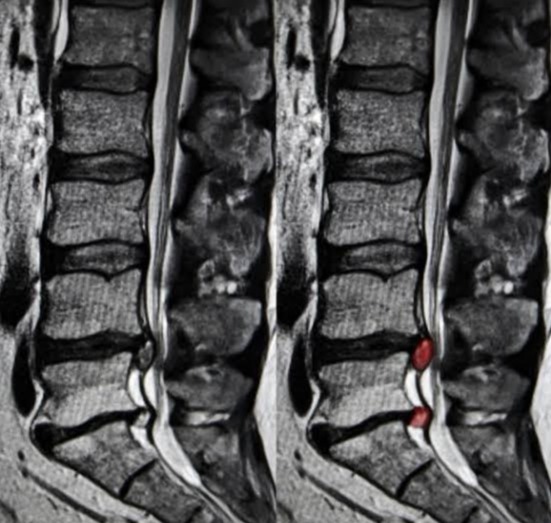

而明确是否存在腰椎间盘突出的检查,以ct和核磁为主。这两项检查都可以相对来讲,比较明确的判断患者的腰椎间盘是否突出突出的位置是否涉及到了神经根,之后如果结合患者的症状以及医生的查体,三者互相印证,就能判断患者是否存在着腰椎间盘突出症。